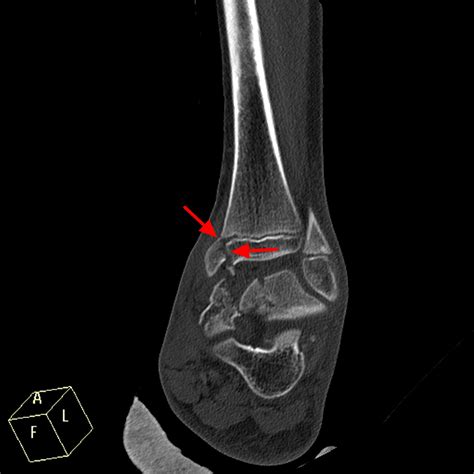

Diagnosing issues related to foot growth plates typically involves a combination of physical examination, imaging studies, and medical history. Common diagnostic tools include X-rays, MRI scans, and CT scans, which can provide detailed images of the growth plates and surrounding tissues. Treatment options vary depending on the severity and type of injury but may include: